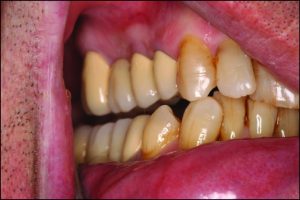

Occlusal discrepancies negatively affect the success of the prosthesis. In partially edentulous cases, due to reasons such as loss of teeth at different times or prolonged edentulism, the remaining teeth tend to tip, drift, or supra-erupt into the edentulous spaces (Figure 9-6).

Figure 9-6. In a patient who has been edentulous for a long time, positional changes in the natural teeth lead to occlusal discrepancies.